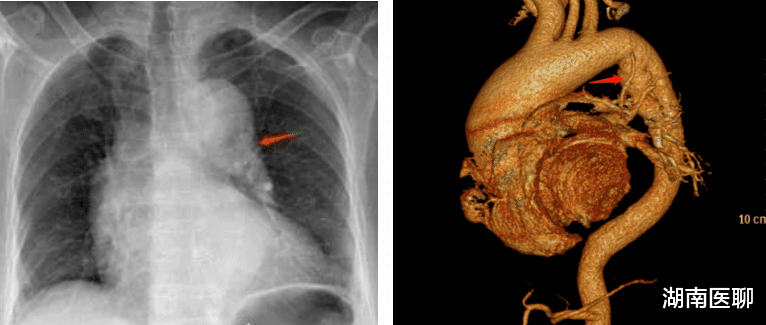

周某 , 女 , 70岁 , 在家劳作时突发背部剧烈疼痛 , 呈持续性 , 活动受限 , 伴恶心 , 呕吐两次 。 因既往有十余年背痛病史 , 遂来石门县人民医院康复科门诊就诊 , 接诊医师正是石门县人民医院康复科唐植纲主任 , 经验丰富的唐主任当时就觉得“这次背痛不一般!” 。 立即予以胸部X线检查 , 结果提示:心影明显增大 , 主动脉增宽 , 主动脉夹层?多个胸椎及L1椎体压缩改变 。

那是否考虑主动脉夹层?还是说背痛是因为胸腰椎压缩性骨折引起?根据患者症状 , 结合血压181/103mmHg, 唐主任认为首先应该排除致命性心血管疾病“主动脉夹层” , 马上建议患者至心血管内科十八病区进一步诊治 , CTA明确诊断为B型夹层 。